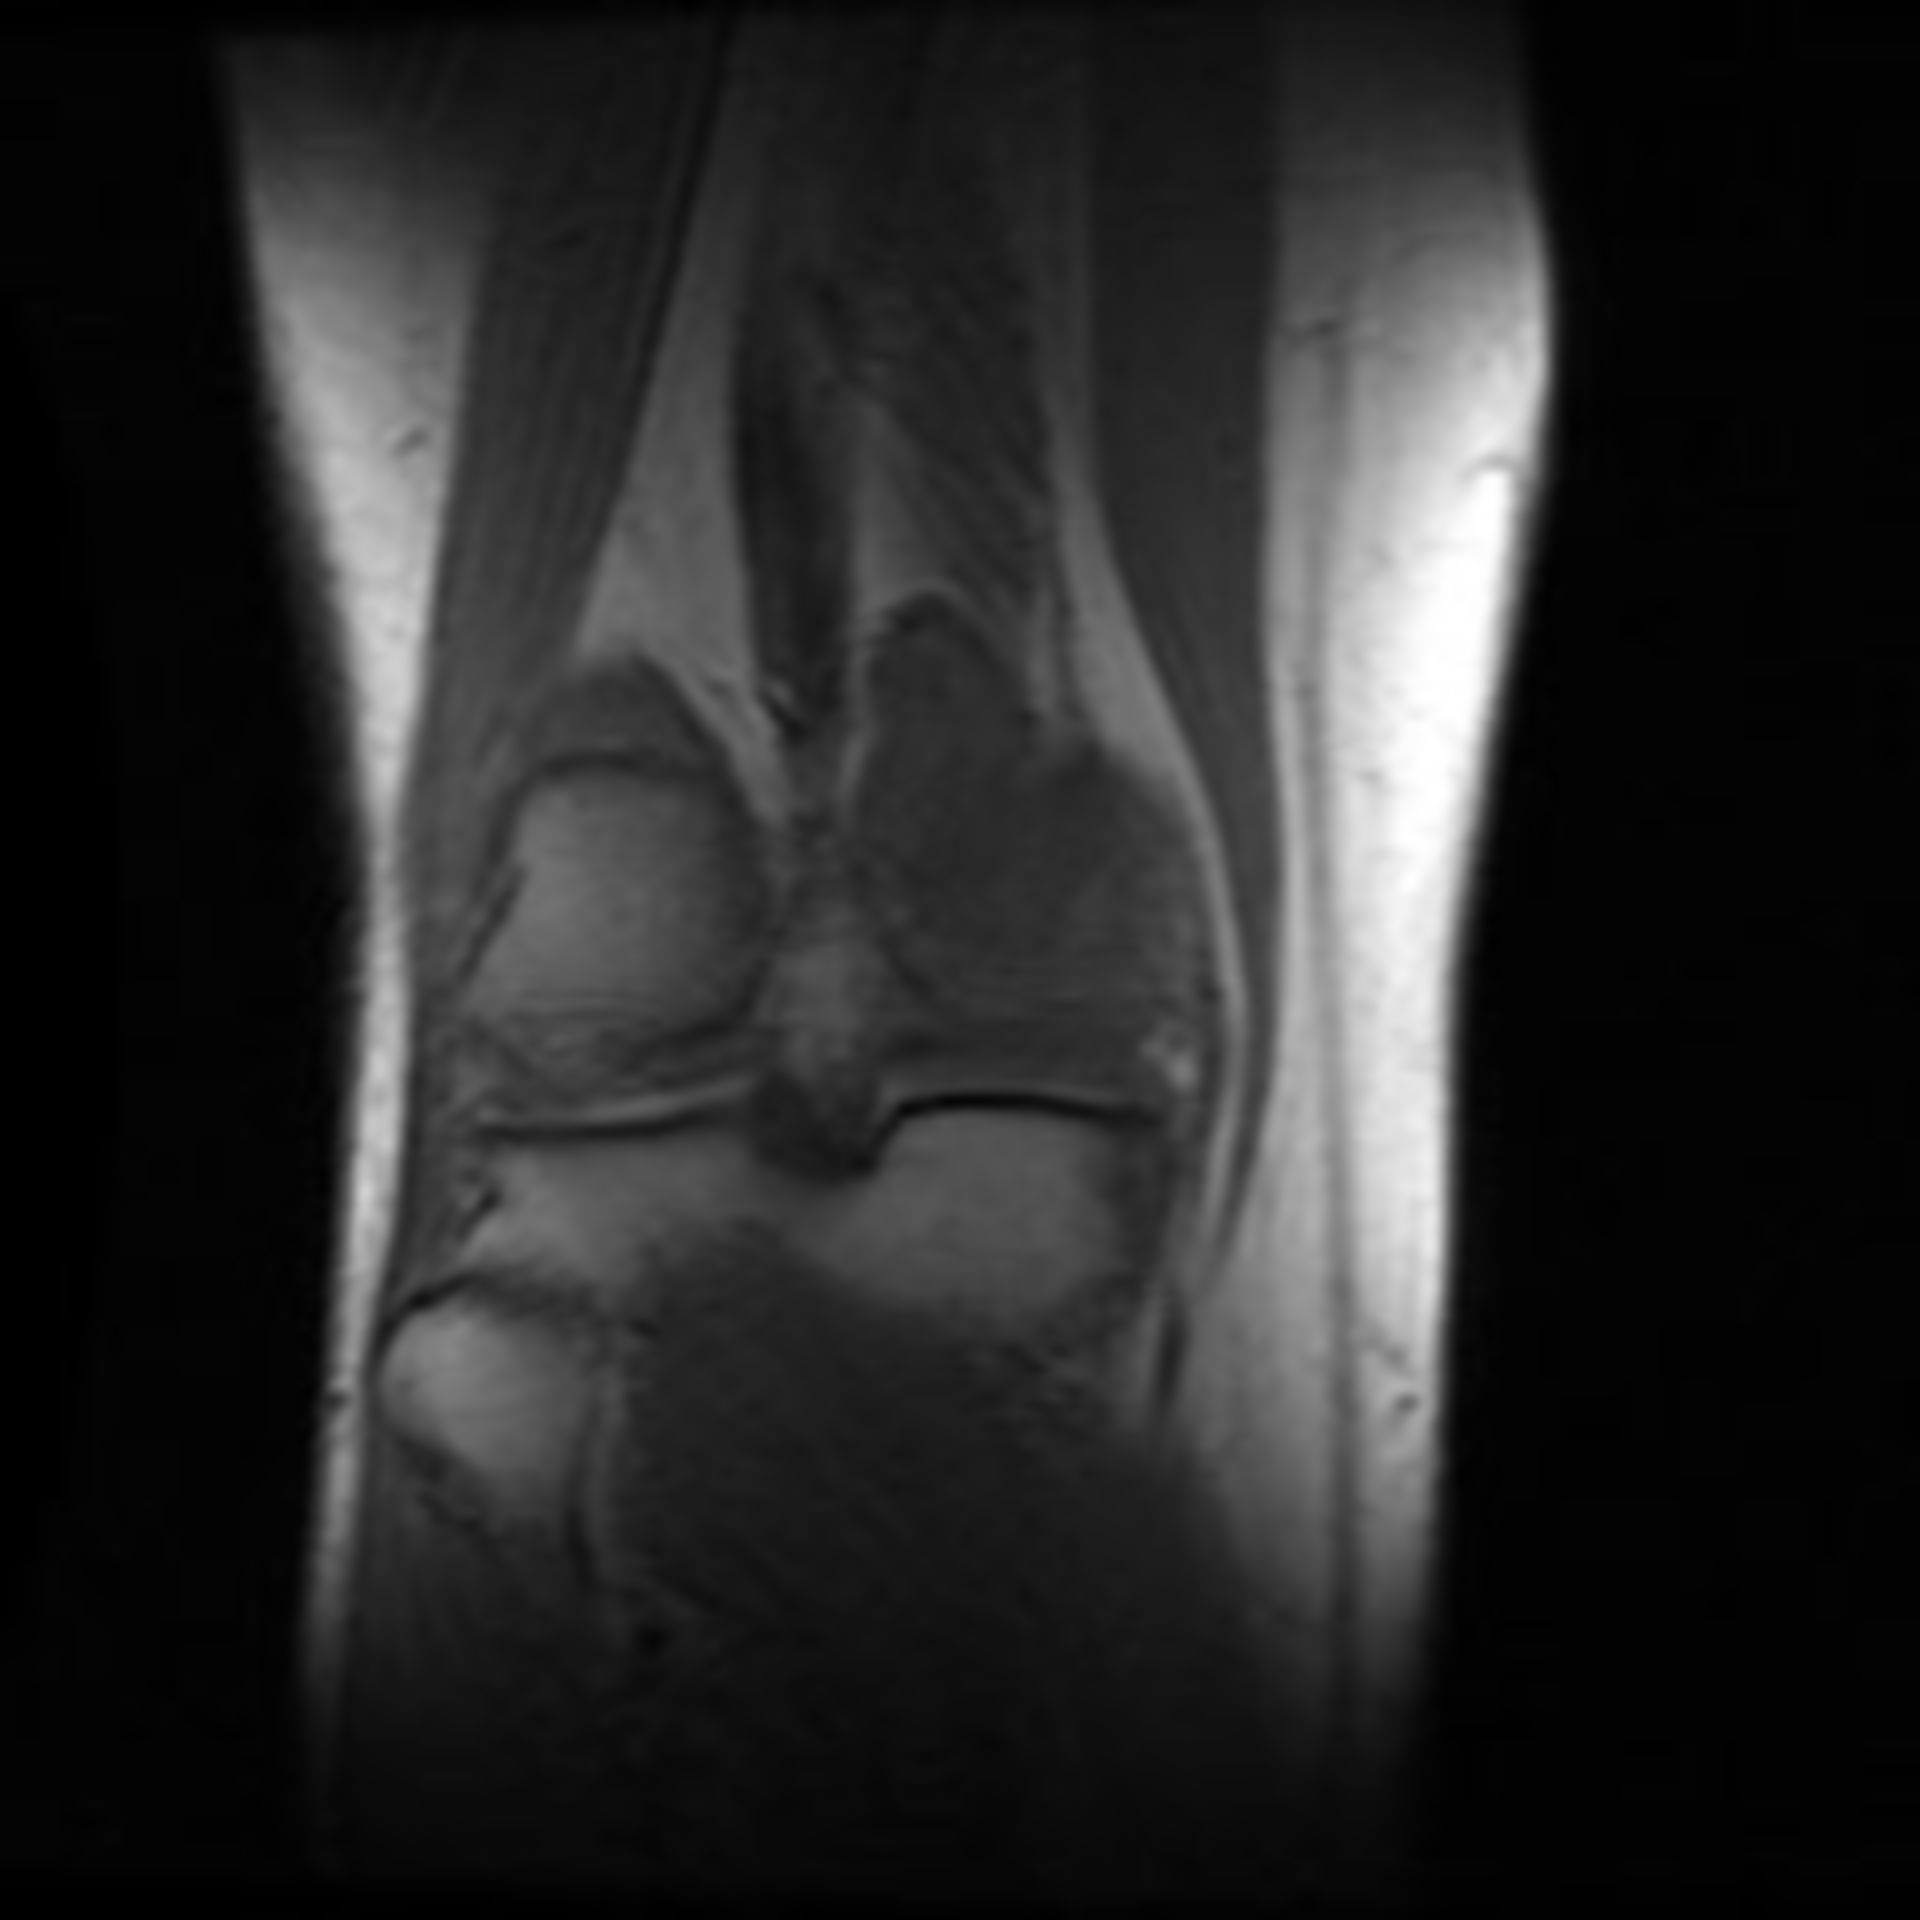

MRT Knie – DocCheck MRT Niere3 – DocCheck

MRT: Knie – DocCheck MRT in der Krebsmedizin

MRT Knie links HWS ARTHROSE, MRT Stockfotografie – Alamy

MRT Knie links MRT der akuten MS Stockfotografie – Alamy

Mrt Bilder – Meniskusriss? (Knie, Orthopädie, Chirurgie) (16/34) MRT Schädel in Sagittalebene, T₂‐gewichtet – DocCheck

MRT Knie links Mrt Bilder Schulter Sehnenriss – Captions Blog

MRT: Knie – DocCheck MRT Schädel – DocCheck

Knee Joint Mri Stockfotos und -bilder Kaufen – Alamy MRT Thorax – DocCheck

MRT: Knie – DocCheck MRT Knie links

MRT Knie linksสถานีMRTแทบแตก? คนเยอะมาก รถไฟไทย🇹🇭พามาดูความลึกความยาวสถานีสามยอดไทยสร้างได้ไง!ความลึกเท่าตึก3ชั้น😯